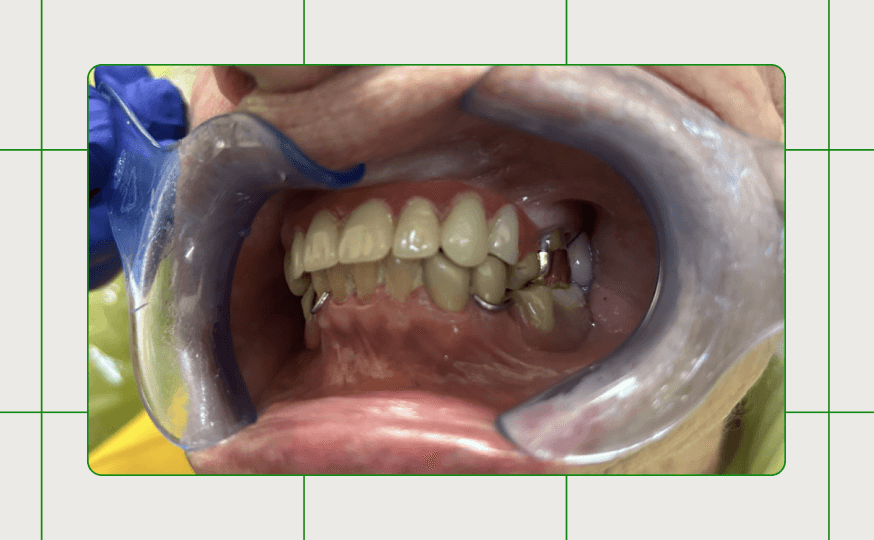

Figures 5a, 5b, 5c:

Figure 5a, 5b, 5c: The maxillary partial denture seated in the patient’s mouth.